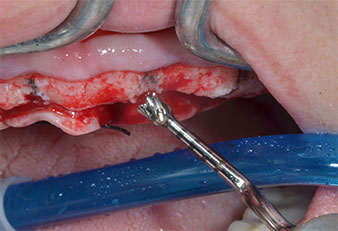

Piezomed I2A/I2P instruments

Fig. 4: The next step is pilot enlargement with the Piezomed I2A/I2P instruments, which are applied in a rotary horizontal movement.